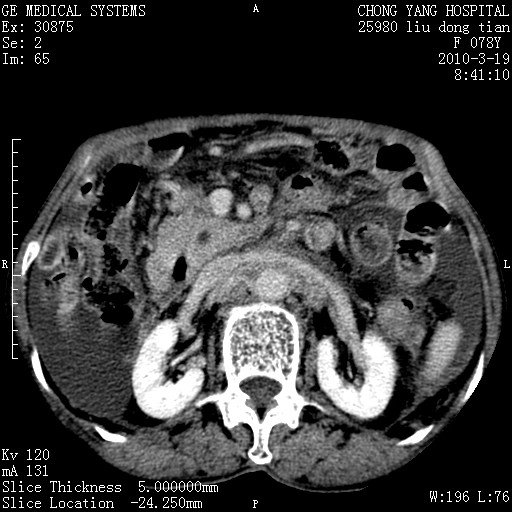

标题: CT25199:F 78Y 腹胀半年 消瘦乏力 [打印本页]

胆囊壁增厚并明显强化,胆囊癌伴多发转移瘤可能性大,淋巴瘤不除外,右肾囊肿,胸腹水.

考虑nhl,肝、脾、腹膜腔及腹膜后多发淋巴结受侵,腹水,右肾囊肿,慢性胆囊炎,右侧少量胸腔积液。

首先考虑恶性淋巴瘤 。

胰头有肿块形成,胰头ca伴肝脾、腹膜腹膜后转移

胆囊有软组织影有强化,支持胆囊癌,肝脾、腹膜后淋巴结转移。

nhl的淋巴结多围绕主动脉,而且主动脉会移位,所以不考虑nhl。

分开来讲:肝左叶、尾叶病灶有不均强化像肝癌;

脾脏病灶无强化,像多发囊肿或淋巴管瘤,不除外淋巴瘤(低强化);

胆囊增生性病变:胆囊癌,腺肌增生症,慢性胆囊炎;

肝门、胰腺头、腹膜后多个团块: 淋巴瘤,转移;

腔静脉肝内段细小有无布加可能?

一元论最好了 淋巴瘤所致改变; 胆囊癌转移不像,胆囊周围肝组织清晰,肝癌淋巴结转移?三元论都不止。

胰头ca伴肝脾、腹膜腹膜后转移!

最后报的胰头癌多发转移,脾脏单独考虑囊肿或淋巴管瘤。